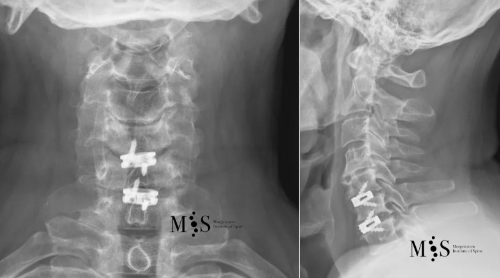

Post-operative X-rays showing an interbody cage at two separate cervical disks after placement with endoscopic fusion surgery

of the cervical spine and was discharged from the hospital in less than 24 hours after surgery.

Clinical case example

This 49 years-old patient presented with a migrated cervical herniation at level C4/C5 and an unstable disk at C5/C6. En endoscopic cervical decompression was performed to remove the herniation and two intervertebral cages were placed endoscopically using a a skin incision of just 2 cm length. Post-operatively, the patient recovered very quickly and was discharged from the hospital within a day after surgery.